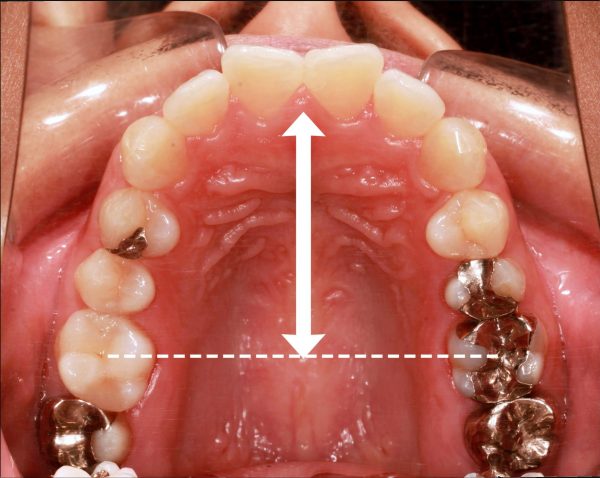

噛めない!「 手術しないで治してほしい 」18歳 男性 骨格性開咬

18歳の 男性です

「 噛めないので、治してほしい 」との事で来院されました。

親知らずを除いて28本の歯の内、奥歯5本しか嚙み合っていません。

23本の歯が 宙に浮いている状態です

レントゲン写真を見てみると、

上の歯が それぞれ前方に大きく傾斜して、前に押し出されています。

また、骨格的な 開咬の状態で、顎が下方向に 開いてしまっています。